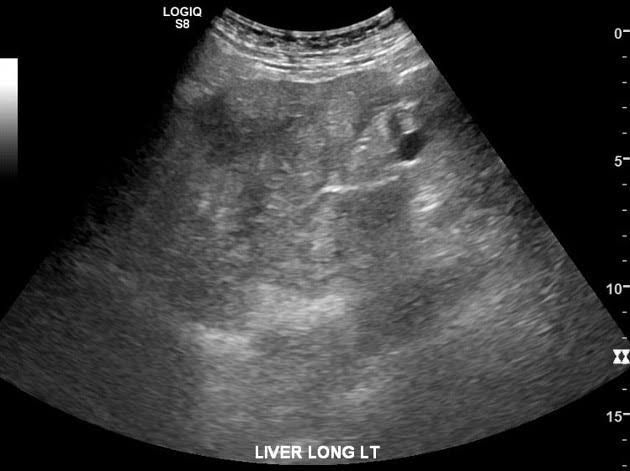

Steatohepatitis is an advanced stage of nonalcoholic fatty liver disease (NAFLD). If you have fatty liver disease, your body has begun storing excess fat in your liver. This doesn't always cause problems for people. But when it does, it's called steatohepatitis.